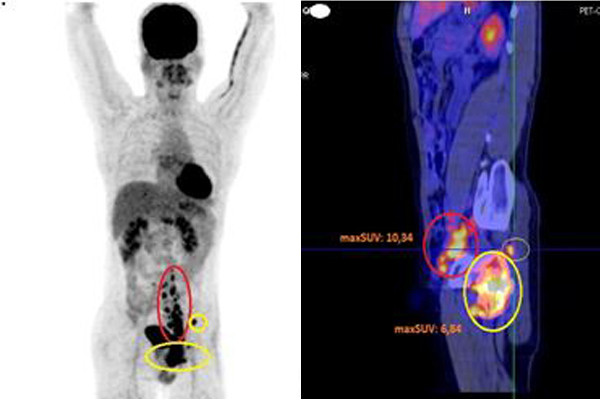

| Kết quả điều trị sau 4 tháng |

Kết quả chụp PET/CT lần 2 cho thấy, cả số lượng và kích thước hạch đều giảm, trong đó hạch dọc động mạch chủ bụng, bẹn trái đã giảm còn 1x2 cm, hạch vùng hố chậu trái còn 3,2x2,1x2 cm. Tuy nhiên xương chậu trái vẫn bị tổn thương nhiều, phá hủy xương và xâm lấn phần mềm xung quanh.

Ở các liệu trình điều trị tiếp theo, bệnh nhân đáp ứng tốt với hoá chất, các tổn thương đa ổ không còn nhìn thấy, khối u nhỏ dần.